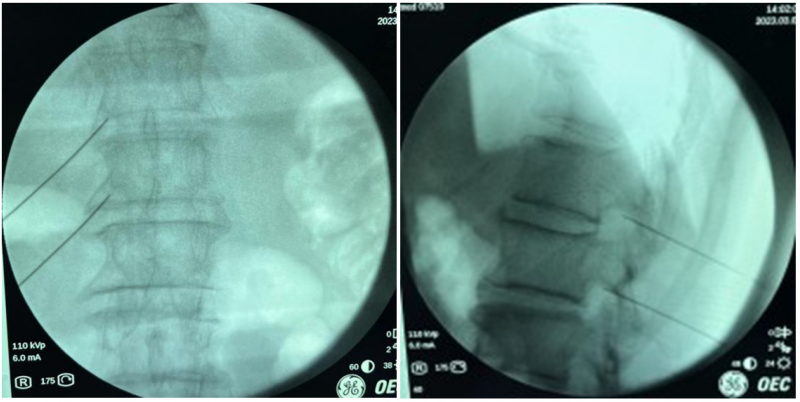

疼痛科高建东团队对刘大爷的病情进行综合评估,考虑患者目前肿瘤多发转移状况,家属难以接受手术切除方案,放化疗短时间内无法解决疼痛问题,综合考虑后制定了行腰1、2背根神经节脉冲射频消融的治疗方案,调制神经消除神经水肿,力求用最快的速度达到最好的止痛效果。这种治疗方案比普通的椎间盘突出射频消融要复杂的多,因为这种方案的进针针尖要尽可能靠近神经根才能对神经有调制作用,又不能过近损伤神经,鉴于老人痛苦度极高,方案确定后当天下午即刻实施治疗方案,术前利用C型臂导视下定位进针点和进针路线,顺利地将射频针精准放至射频靶点,连接电极、测试、复制患者疼痛症状后,给与42℃下脉冲射频模式2分钟,整个过程用时35分钟,治疗结束后刘大爷的疼痛很快消失了。刘大爷笑道,“今晚终于可以睡个好觉了。”停服止痛药物,观察36小时患者疼痛症状无反复,顺利出院。

C型臂透视射频针穿刺到靶点位置。